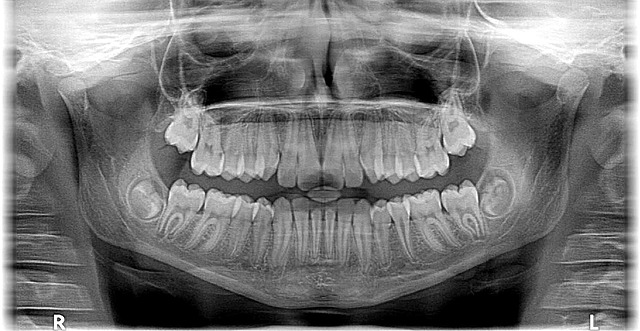

When preparing for your first orthodontic consultation with an orthodontist in McAllen, TX, it’s beneficial to take a few simple steps. Begin by gathering all your medical records and x-rays from previous dental visits. These documents will help your orthodontist understand your oral history and current state of teeth alignment. Additionally, make a list of any questions or concerns you have regarding your bite, teeth, or jaw pain. This proactive approach ensures a productive consultation where you can gain valuable insights into potential treatment options.